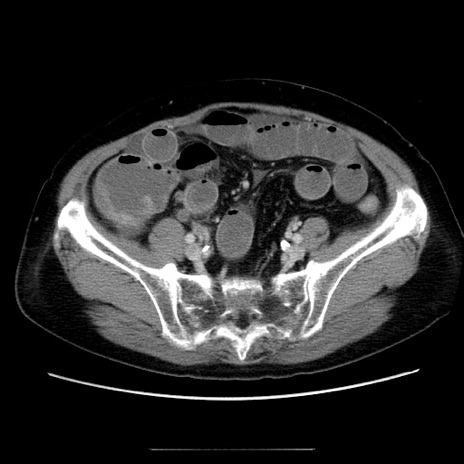

症例5(横断像)

【症例】70歳代女性

【主訴】お腹が張る

【現病歴】1週間くらい前から腹部膨満の自覚あり。昨日夜から増悪したため、本日救急外来受診。

【身体所見】意識清明、BT 36.5℃、BP 165/106mmHg、HR 80bpm、SpO2 98%、腹部:膨満、軟、自発痛・圧痛なし、触診にて不快感あり、腸蠕動音:減弱

【データ】WBC 12600、CRP 1.04